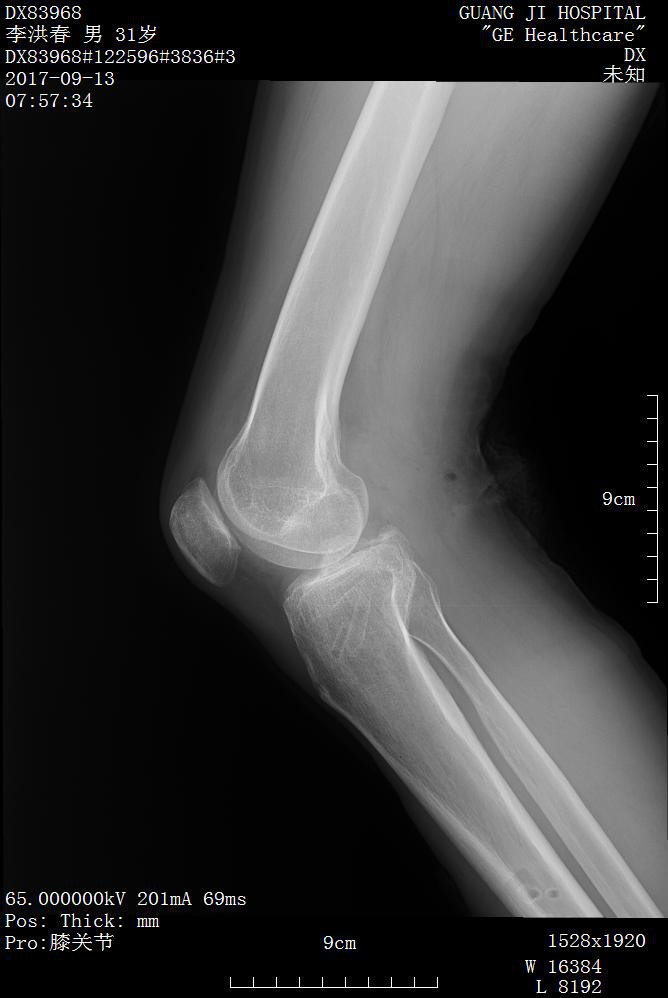

影像资料如下:

诊断:

1.右膝关节后交叉韧带止点撕脱性骨折(2 型)

2.右髋关节脱位

3.右胫骨骨折

4.全身多处软组织挫裂伤